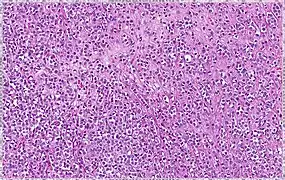

Solid | 10% | Sheets of classical-appearing cells with little intervening stroma | |

Pleomorphic | Classical-appearing but with pleomorphic cells. It may include signet-ring cells, or plasmacytoid cells (pictured) which have abundant cytoplasm and eccentric nuclei. | ![]() |